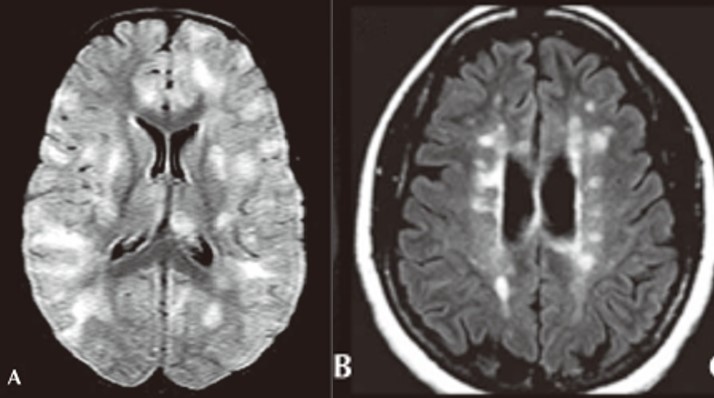

(A) Axial FLAIR sequence showing bilateral, globular, hyperintense lesions in cortical gray matter, centrum semiovale, and deep gray nuclei. (B) Axial FLAIR sequence showing ovoid, periventricular hyperintensities typical of MS plaques. Lee, Y. J. Acute disseminated encephalomyelitis in children: differential diagnosis from multiple sclerosis on the basis of clinical course. Korean J. Pediatr. 54, 234–240 (2011).